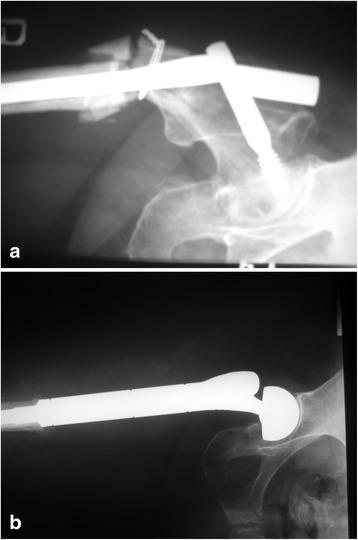

Breast, prostate, and lung cancers are the most common primary tumors that metastasize to bones. The most common site of the lesions is the proximal femur; sporadically, they do occur in bones distal to the knee and elbow. After the surgery, all the patients could walk, most of them without crutches. The pain, rated on a VAS scale, decreased significantly, and the Karnofsky score improved. We observed that joint mobility and the strength of the muscles in the limbs allowed for normal functioning. Postoperative complications including infections and local tumor recurrences were rarely observed.

The use of modular prostheses is an adequate method of treatment in patients with bone metastases. A radical resection of the tumor, which prevents local recurrences and loosening of implants, gives good outcomes. Reduced joint mobility resulting from muscle attachment cutting is well tolerated and concerns mainly patients that underwent operations on the humerus.

乳腺癌、前列腺癌和肺癌是最常见的转移至骨骼的原发性肿瘤。最常见的病变部位是股骨近端;偶尔也会出现在膝部和肘部远端的骨骼。手术后,所有患者都能行走,大多数患者无需拐杖。根据视觉模拟评分法(VAS)评定的疼痛显著减轻,卡氏评分改善。我们观察到关节活动度和肢体肌肉力量使功能正常。很少观察到包括感染和局部肿瘤复发在内的术后并发症。

使用模块化假体是治疗骨转移瘤患者的一种适当方法。肿瘤的根治性切除可防止局部复发和植入物松动,效果良好。因切断肌肉附着而导致的关节活动度降低耐受性良好,主要影响接受肱骨手术的患者。